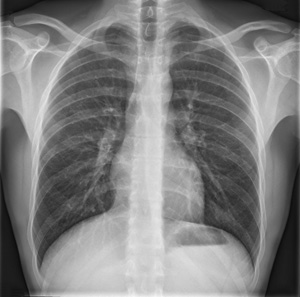

xray grHij schrijft zoals voorheen een aanvraag voor onderzoek en voegt daar klinische gegevens, de diagnose waaraan hij denkt en het type onderzoek toe. Omdat het met de snelle veranderingen in de technologie niet altijd mogelijk is up-to-date te blijven over alle mogelijke onderzoeken, kan steeds het advies van de radioloog gevraagd worden. Om eventueel vertragingen in het onderzoek te vermijden, wordt aangeraden in geval van twijfel over het meest geschikte onderzoek steeds contact op te nemen met de radioloog. Zo kan in onderling overleg beslist worden welk onderzoek best uitgevoerd wordt.

Het meest tastbare gevolg is er wellicht voor de patiënt. Stel dat die een afspraak heeft om een CT-scan te laten maken, maar de radioloog vaststelt dat er eigenlijk een MR moet genomen worden. In dat geval zijn er twee mogelijke scenario's. In het eerste scenario heeft het ziekenhuis waar de patiënt zich aanbiedt, geen MR ter beschikking. De patiënt moet dan een nieuwe afspraak maken in een ander ziekenhuis. In het tweede scenario heeft het ziekenhuis wel degelijk een MR, maar moet de patiënt toch een nieuwe afspraak maken omdat het niet mogelijk is om meteen naar de MR door te schuiven. In beide gevallen is er sprake van meer tijdverlies en ergernis voor de patiënt. Het voordeel voor de patiënt is dan weer dat hij weet dat het meest optimale onderzoek uitgevoerd zal worden.